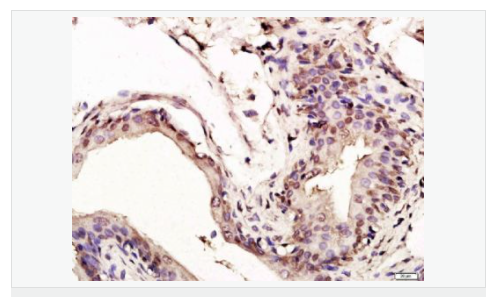

| 產(chǎn)品應(yīng)用 | WB=1:1000-2000 ELISA=1:1000-5000 IHC-P=1:100-500 IHC-F=1:100-500 Flow-Cyt=1ug/Test ICC=1:100-500 IF=1:100-500 (石蠟切片需做抗原修復) not yet tested in other applications. optimal dilutions/concentrations should be determined by the end user. |

| 細胞定位 | 細胞核 細胞漿 |